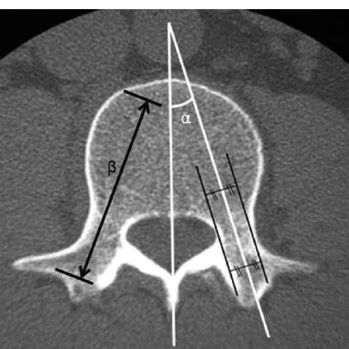

单一正位、单一斜位经皮椎弓根钉植入方法

更多精彩好文请下载骨今中外APP阅览

骨今中外 2021-03-25